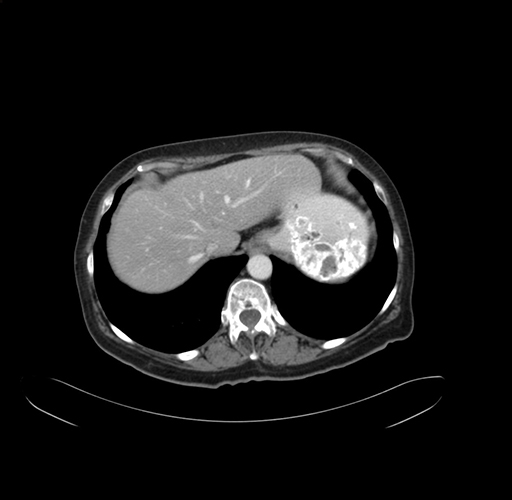

Pre-Chemo: Axial Venous